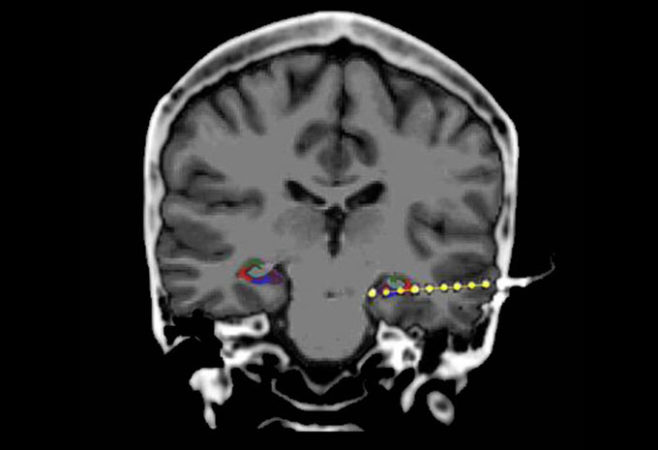

Using implanted electrodes (shown in yellow), researchers spied on brain activity as people formed and recalled memories. The team found that just before a person remembered a face or object they’d seen earlier, the hippocampus underwent “ripples” of activity (colored areas).

Weizmann Institute of Science